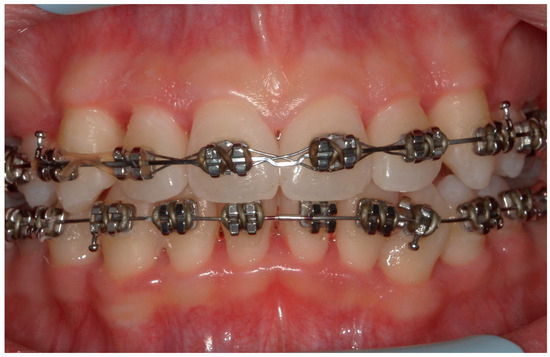

4.1. Case 1

4.2. Case 2